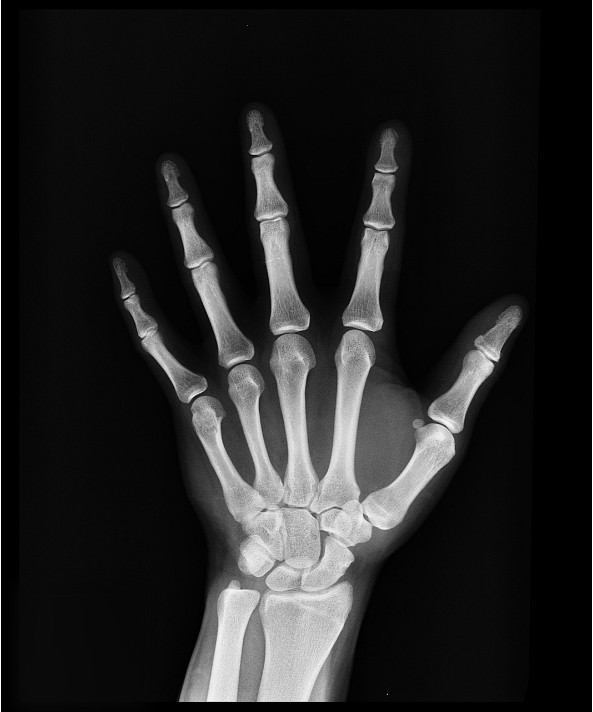

골절 위험 증가

골다공증의 가장 대표적인 초기증상은 골절 위험의 증가입니다. 뼈가 약해지면서 작은 충격이나 낙상으로도 쉽게 골절이 발생할 수 있습니다. 특히 손목, 고관절, 척추, 발목 등의 부위가 자주 골절되므로 주의가 필요합니다. 골절이 발생하면 통증, 부기, 혈종, 움직임 제한 등의 증상이 나타납니다. 골절이 의심되면 즉시 병원에 가서 X-선 검사를 받아야 합니다. 골절이 확진되면 골절 부위에 깁스나 부목을 씌우고, 필요한 경우 수술을 받아야 합니다. 골절이 치료되고 나서도 골다공증 치료를 위해 약물이나 운동 요법을 받아야 합니다.